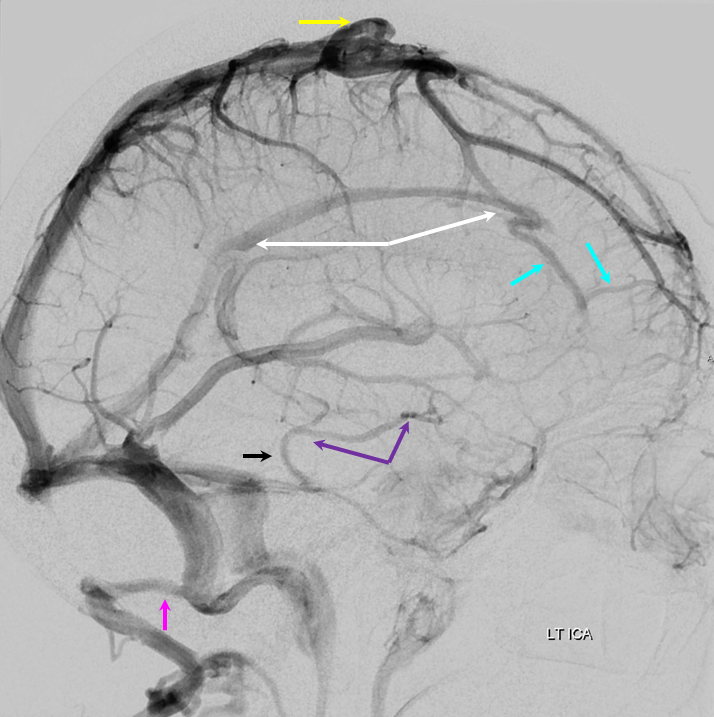

Some arrows. Open white arrows — septal veins on the medial aspect of frontal horn. Thick white arrows — longitudinal caudate venous arcade. Black arrow — direct lateral vein, prominent because of hypoplasia of the posterior segment of the left longitudinal caudate vein. Thin white arrows are transverse/ medullary veins

Below is an example of as large an inferior sagittal sinus (white) as one is likely to ever see under non-pathologic circumstances. Why is this sinus so large? Again, the answer is that veins are like rivers — the inferior sagittal sinus happens to be receiving a completely benign, nonpathologic mesial anterior frontal vein (blue arrows). However, the increased inflow into the Galen system has likely resulted in alternate drainage of the basal vein (purple) into the superior petrosal sinus via the lateral mesencephalic vein (black) — see deep venous system and veins of posterior fossa pages for more info. Also notice a large emissary vein (pink)